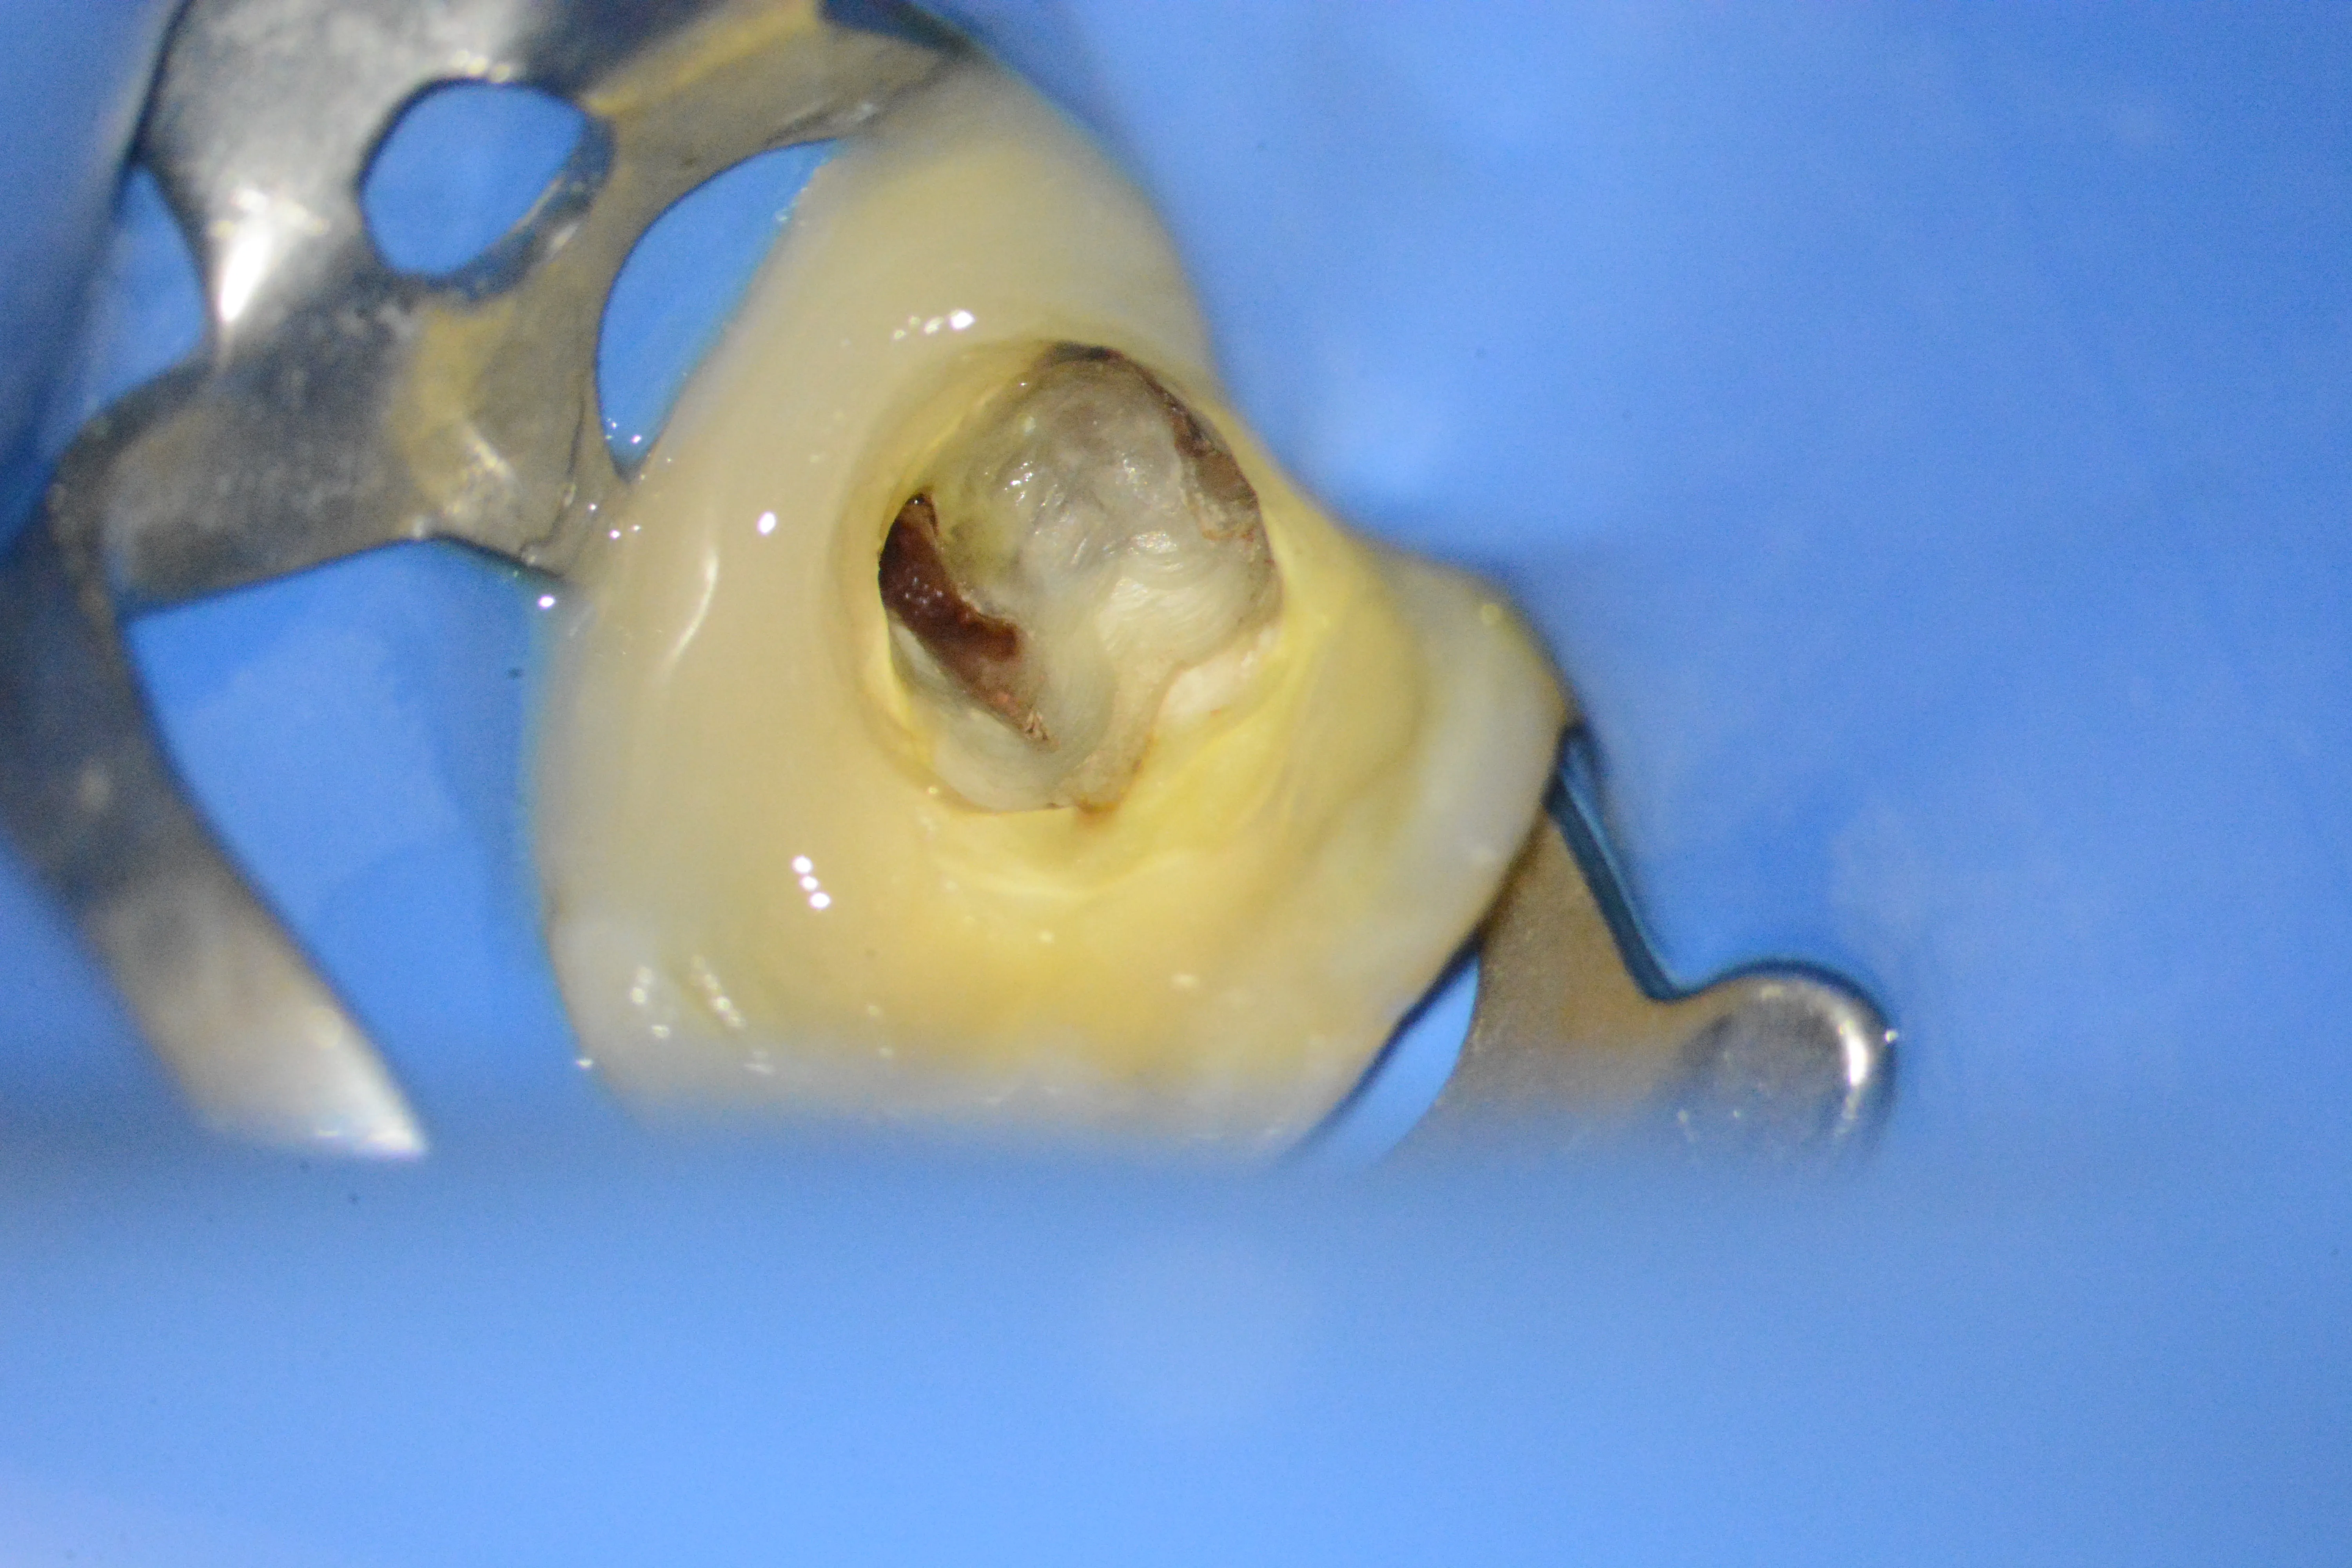

3 – Exereză parțială dentină alterată

4 – Inflamație pulpară ireversibilă